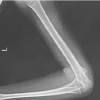

A 76-year-old woman with a body mass index of 20.9 kg/m2 with bilateral knee pain visited our hospital. Pre-operative characteristics of the patient are shown in Table 1. Preoperatively, the right knee had valgus deformity Krakow classification Type 2 [4] and the left knee had varus deformity (Kellgren-Lawrence classification Grade 4) (Fig. 1).